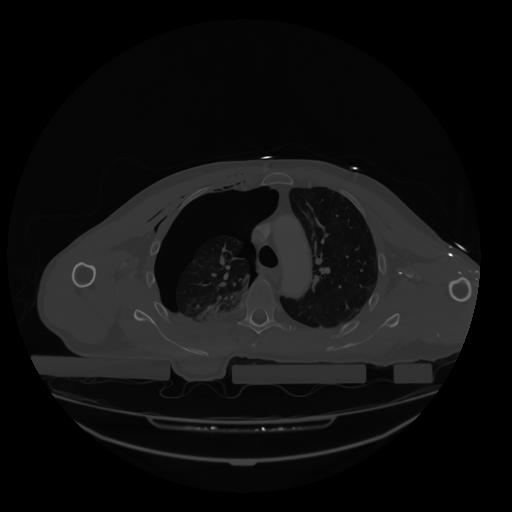

28 CUERPO,CE,Vol,2.0,CUERPO,,